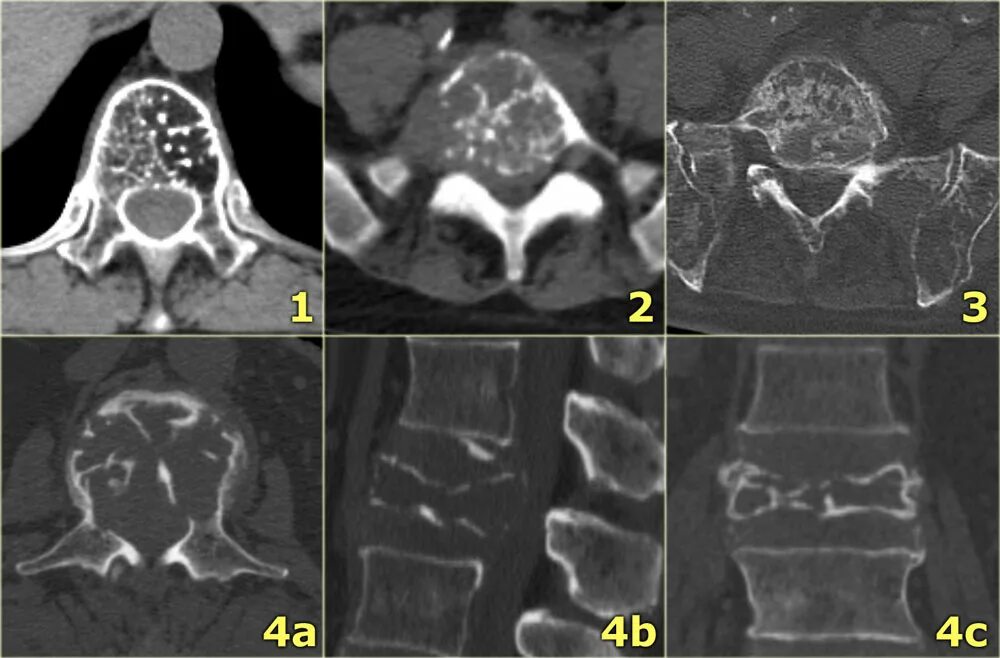

Заболевание кт